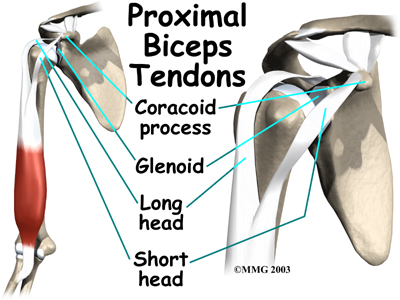

The biceps muscle goes from the shoulder to the elbow on the front of the upper arm. Tendons attach muscles to bone. Two separate tendons connect the upper part of the biceps muscle to the shoulder. One tendon connects the lower end of the biceps to the elbow.

The lower biceps tendon is called the distal biceps tendon. The word distal means that the tendon is further down the arm. The upper two tendons of the biceps are called the proximal biceps tendons, because they are closer to the top of the arm.

The upper (proximal) end of the biceps has to the shoulder. The main attachment is the long head of the biceps. It connects the biceps muscle to the top of the shoulder socket, called the glenoid. The short head of the biceps angles up and in to its attachment on the corocoid process of the shoulder blade. The corocoid process is a small bony knob in the front of the shoulder.